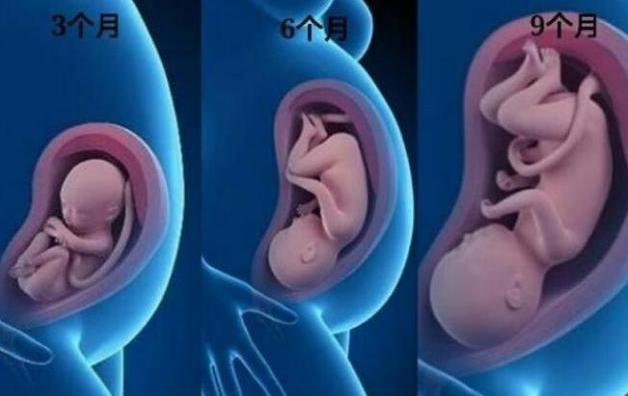

有人说,女性在分娩时是最大、最高级的痛苦,其实,在怀孕的过程中也是很难熬的。尤其在孕期的这三个阶段:孕3个月、孕6个月和孕9个月。也许很多人不理解为什么是这三个阶段,其实这三个阶段非常有特点,至于它们之间有何不同,下文会给您详细的答案!

1、怀孕3个月

2、怀孕6个月

3、怀孕9个月

怀孕的女性,生活节奏不可能会与之前的一样,毕竟肚子里的胎儿一天天地长大,尤其在怀孕3个月,6个月和9个月时,孕妇是比较辛苦的,需要忍受各种的不适与煎熬。不过,每次胎检时,得知胎儿一切安好,相信孕妇还是觉得幸福的。总之,还是多多祝福孕妇吧,是她们的伟大,给家庭带来了新的生命。